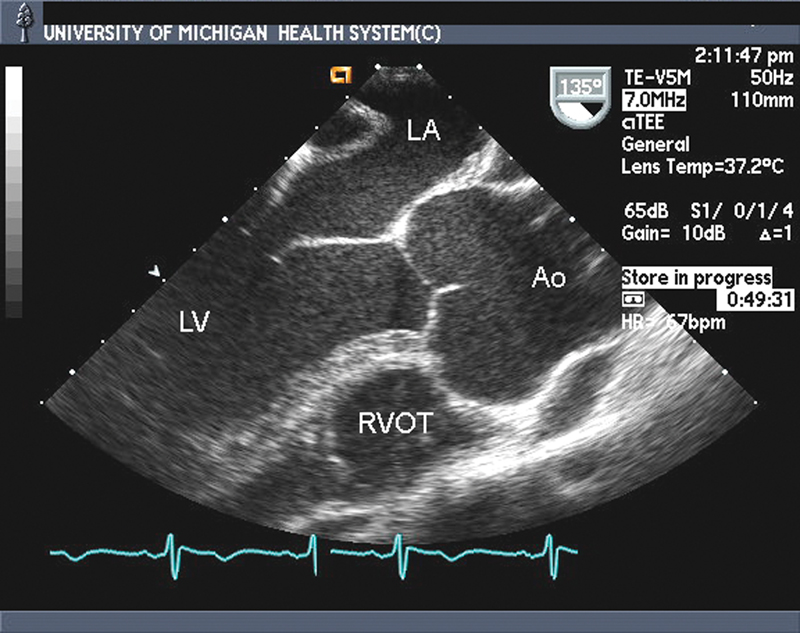

فحوصات تشخيصية لبعض امراض القلب والشرايين التاجية